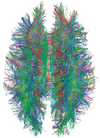

Diffusion tensor DTI Mainly tractography (pictured) by an overall greater Brownian motion of water molecules in the directions of nerve fibers.[28]

• Evaluating white matter deformation by tumors[28]

• Reduced fractional anisotropy may indicate dementia.[29]

White Matter Connections Obtained with MRI Tractography.png